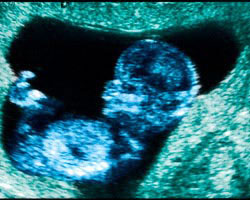

Ecografia de 12 semanas

Na 12ª semana de gravidez a maioria das mulheres realiza a primeira ecografia das três principais que se fazem numa gravidez saudável, de modo que verá os movimentos do seu bebé pela primeira vez.

Um momento especialmente emocionante também para o futuro papá e que irá servir para fizar definitivamente a idade gestacional do feto e a data prevista de parto, que apenas de cumpre à risca em 5% das vezes.

Ecografias que deverão reconhecer os quatro membros, as mãos e pés do bebé, a coluna, aspetos do desenvolvimento do cérebro, o estômago repleto de fluido e a bexiga.

Na 12ª semana de gravidez a ecografia também irá examinar a viabilidade fetal (o batimento do coração) e determinará a espessura da translucência da nuca, uma zona que fica atrás do pescoço que se considera um marcador de alterações genéticas como a síndrome de Down ou a de Turner.

Quando esta medida é superior a 3 milímetros – a medida que se considera normal na décima segunda semana de gestação – pode existir um maior risco de síndrome de Down.

Em consequência, o médico poderia recomendar realizar uma amniocentese a partir da 15ª semana de gravidez para confirmar o diagnóstico.